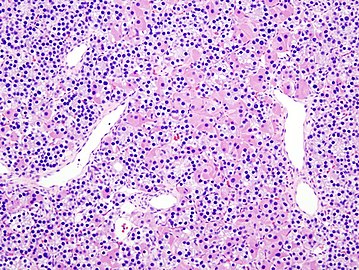

Parathyroid Adenoma

A parathyroid adenoma is a benign tumor of the parathyroid gland. It generally causes hyperparathyroidism; there are very few reports of parathyroid adenomas that were not associated with hyperparathyroidism.[1]